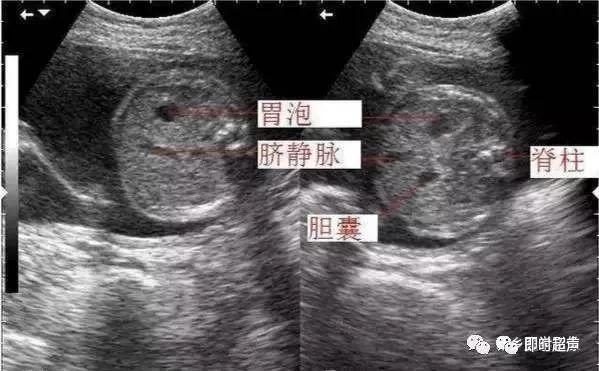

孕13周胎儿二维切面图及彩色血流图

7,胎儿腹围测量标准切面:3.

脑室率:在双顶径切面略向上平行移动的切面(测量侧脑室的标准平面),脑